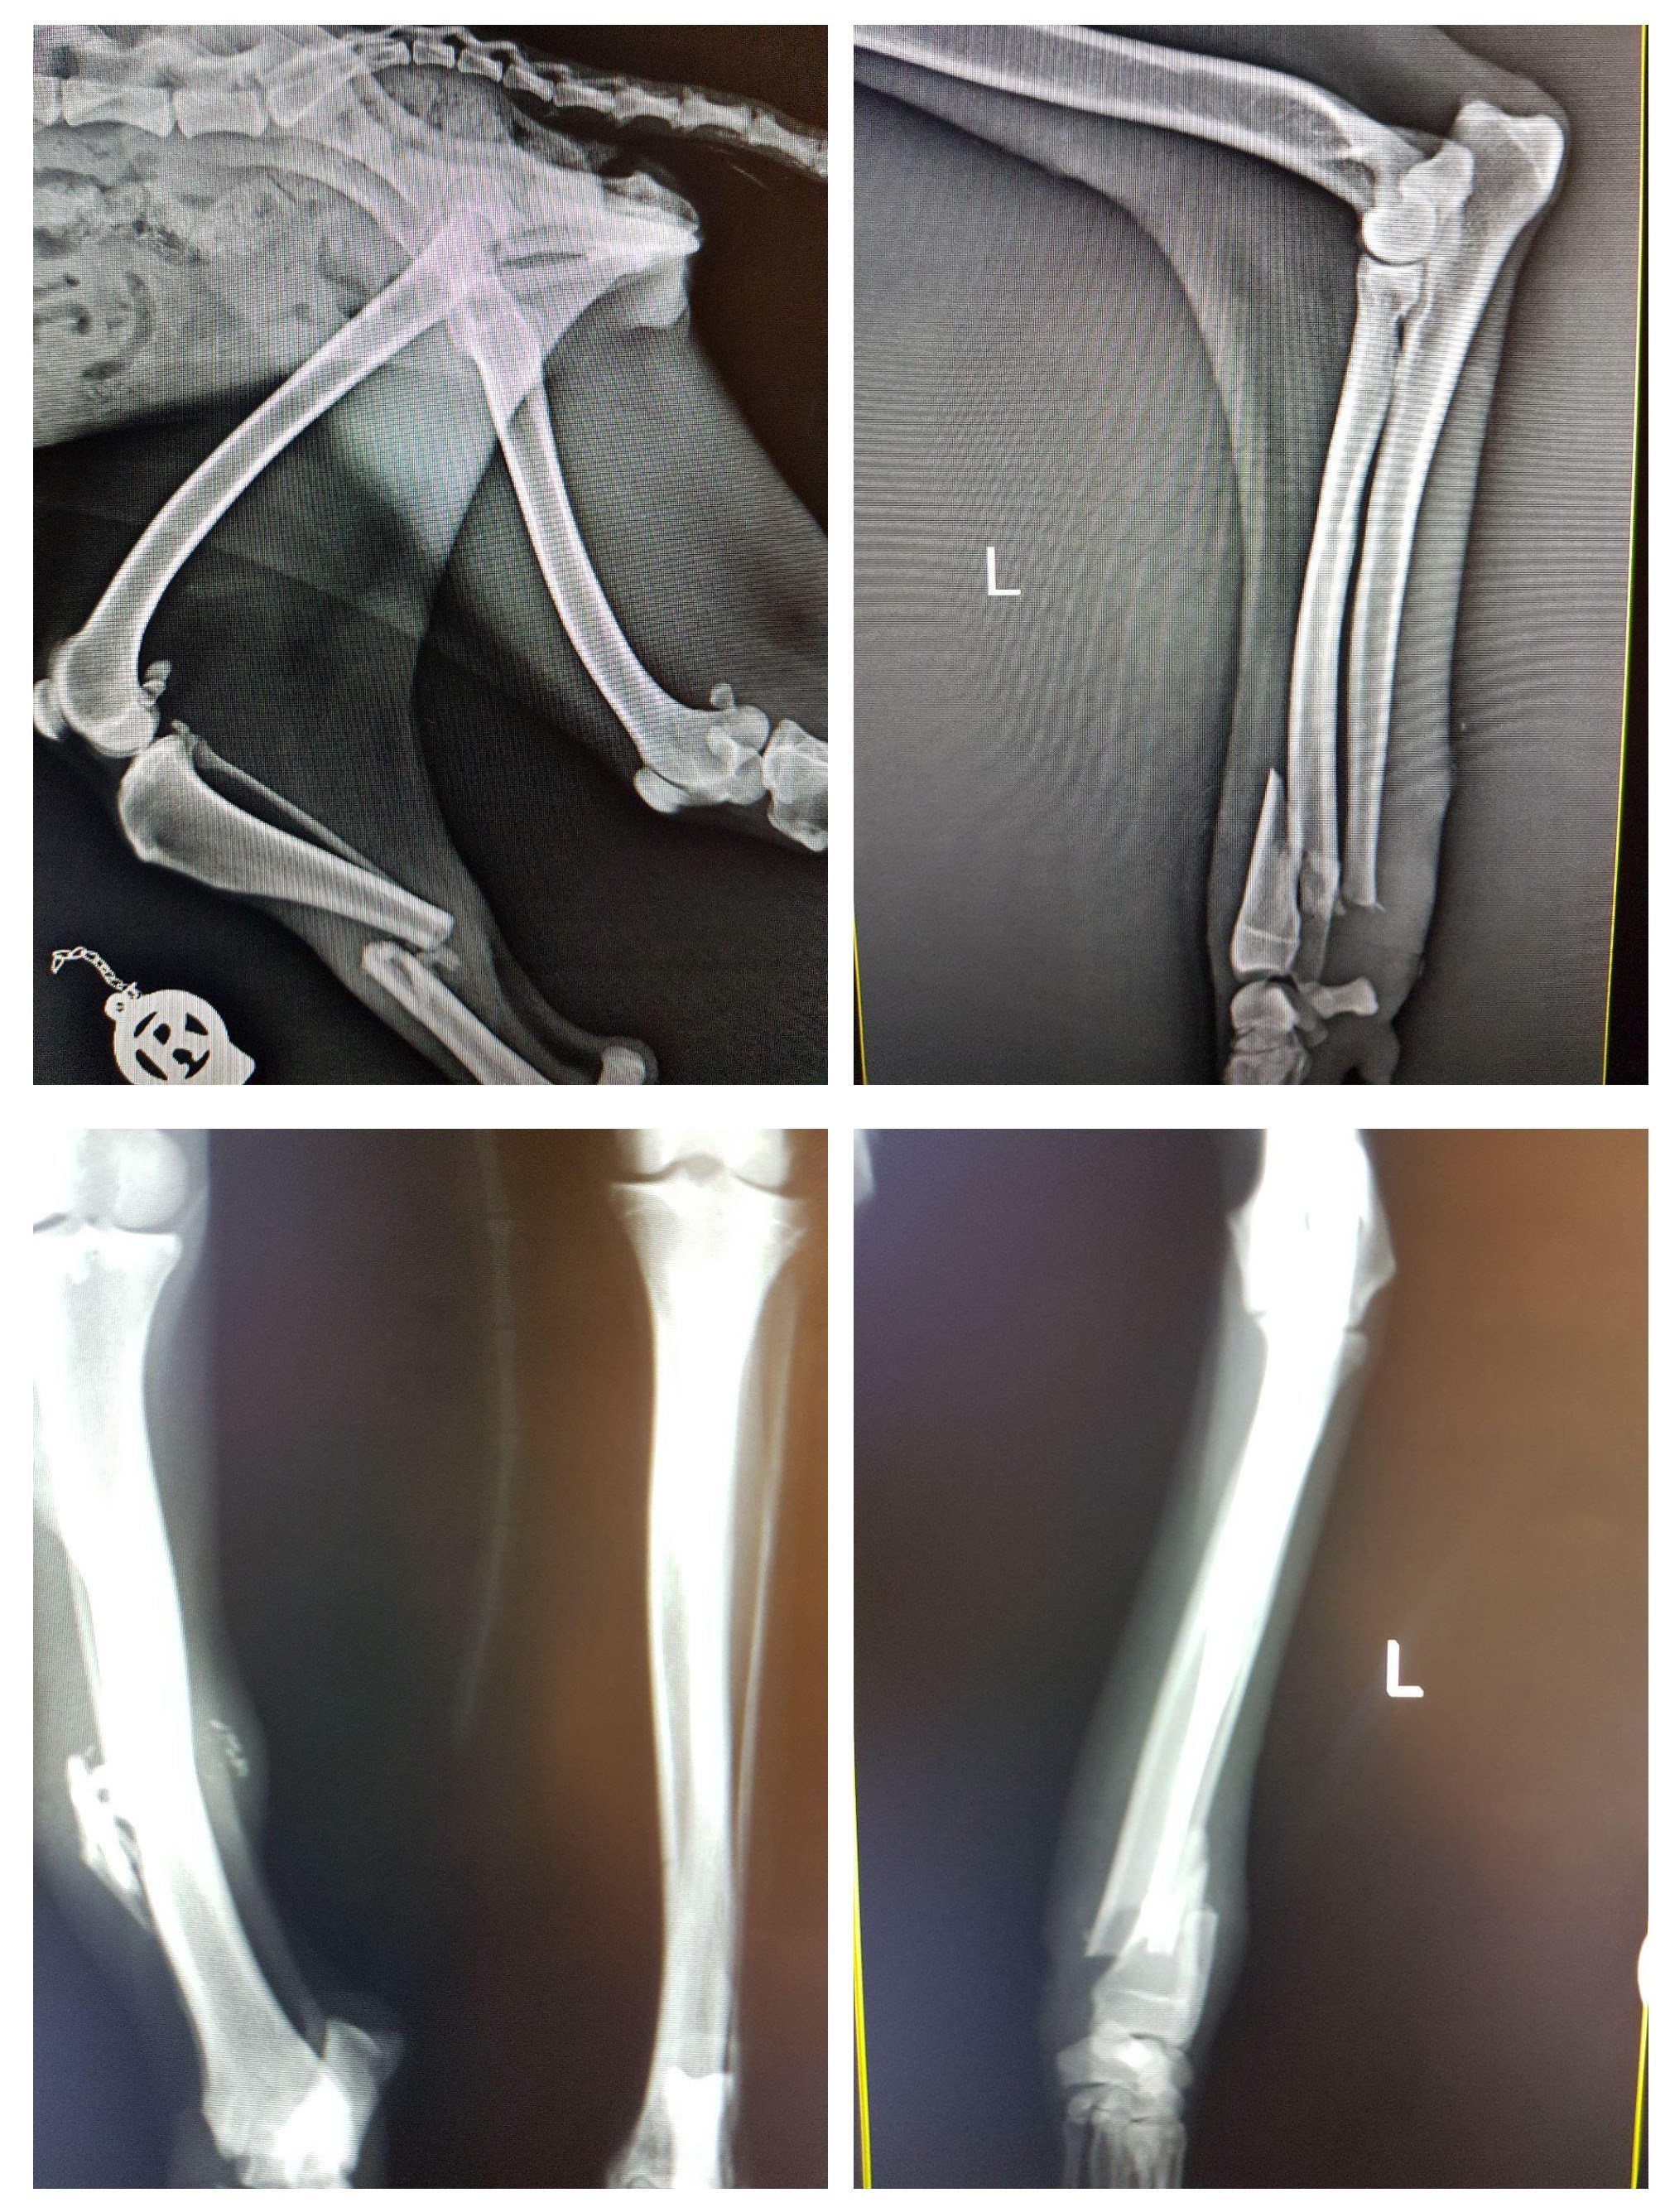

حمیدرضا فتاحیان جراح معالج شغال محمودآباد، درباره عمل جراحی این حیوان به خبرنگار اجتماعی خبرگزاری تسنیم گفت: شکستگی ساعد دست چپ این شغال ماده با استفاده از پیچ و پلیت، و شکستگی پای راست، به منظور تسریع در روند التیام شکستگی، با استفاده از پیچ و پلیت و همچنین پیوند استخوان تحت درمان جراحی قرار گرفت و در جهت کمک به روند درمان گچگیری شد. شکستگی استخوان پاشنه در مچ پای راست به دلیل وجود زخم در ناحیه مچ پای راست، مورد عمل قرار نگرفت که پس از بهبود وضعیت زخم در ناحیه مذکور و همچنین مشاهده وضعیت عمومی مناسب بیمار، در صورت نیاز به مداخله جراحی، در روزهای آتی تحت جراحی قرار خواهد گرفت.